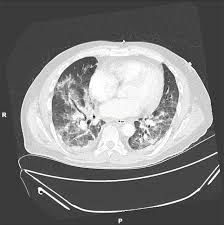

Ct Scan Of The Lungs Axial View Showing Greatly Abnormal Parenchymal Download Scientific Diagram

Postoperative Hypoxaemia Telebrix Aspiration Postgraduate Medical Journal